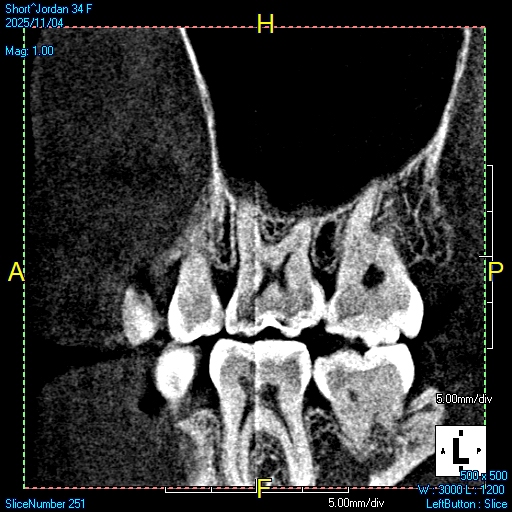

Modern dentistry relies on accuracy, clarity, and detailed information. Cone Beam Computed Tomography, often called CBCT or 3D imaging, provides a complete view of the teeth, jaw, and surrounding structures. This advanced technology helps dentists diagnose problems early and plan treatments. When patients have a CBCT radiograph taken at Brady Dental Group in Amarillo, Texas, they benefit from a more detailed 3D image, gentle techniques, and a dental team committed to comfort and education.

CBCT imaging allows the dentist to look beyond the surface. Instead of relying on flat, two dimensional images, CT technology creates a full three dimensional picture that reveals structures from every angle. This helps guide everything from dental implants to root canal evaluations, and it helps catch issues that cannot be seen with standard X-rays. Many patients say the experience helps them feel more informed, more confident, and more involved in their dental care.

Computed Tomography digital imaging gives a complete, three dimensional view of the mouth. It shows the position of teeth, bone levels, sinus spaces, nerve pathways, and jaw joints. This level of detail helps the dentist diagnose conditions that traditional X-rays may miss.

CT images show the exact shape of the roots, the depth and strength of the bone, and the spaces where infections or cysts may form. They also help identify impacted teeth, fractures, and early signs of bone loss. Because the images display depth and volume, dentists can examine the mouth in ways that were not possible before.

At Brady Dental Group in Amarillo, Texas, CT technology is used for patients who need thorough evaluation and precise planning. The images are clear, detailed, and available immediately for review.

CBCT imaging offers powerful benefits for both the dentist and the patient. They help diagnose problems earlier, plan treatments more accurately, and reduce the risk of complications. Patients appreciate the clarity and the opportunity to see their own anatomy in a way that makes sense.

The process for Cone Beam Computed Tomograph digital X-rays at Brady Dental Group is comfortable and fast. Patients stand or sit still while the machine rotates around the head. The scan usually takes less than a minute. There is no discomfort and no pressure. The digital technology also uses controlled, low radiation while still producing highly detailed images.

Once the scan is complete, the images appear on the computer screen. The dentist can rotate the image, zoom in on small areas, and show different layers of bone and tissue. This makes it easy to explain what is happening beneath the surface and why a certain treatment may be needed.

CBCT imaging is valuable for evaluating teeth that may need root canal treatment. Traditional X-rays sometimes miss small fractures, hidden roots, or deep infections. A CT scan can reveal these details.

CT scans provide valuable information about the jaw joint, often referred to as the TMJ. Patients who experience popping, grinding, or jaw pain can benefit from a CT scan that shows the exact structure of the joint. This allows the dentist to understand the cause of discomfort and create a treatment plan that addresses the problem directly.

Cone Beam Computed Tomography digital X-rays at Brady Dental Group in Amarillo, Texas provide unmatched clarity and information for patients of all ages. Whether you need implants, root canal diagnosis, jaw evaluation, or a detailed assessment for treatment planning, CT imaging supports safe, accurate, and comfortable care.